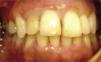

ResultadosDespués de un año se concluyó la rehabilitación que consistió en una corona atornillada de porcelana.

ResultsOne year later, rehabilitation was completed with a screwed-in, fixed porcelain crown.

Después de un año y medio se concluyó la rehabilitación protésica que consistió en una corona implantosoportada atornillada de porcelana feldespática (Noritake®, Japón) con aditamento calcinable y anillo de oro (3i®) (Figura 10).